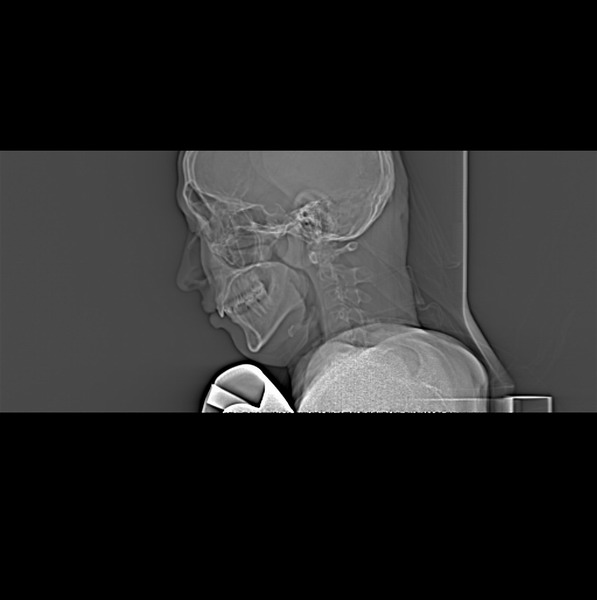

男、30、发现鼻咽部肿瘤侵犯海绵窦,未发现明显淋巴肿。请问国内那家医院治疗鼻咽部肿瘤最好?手术以何种方式为主?病灶可否全部切除?急切期待的大家的帮助。

扫描示鼻咽腔不对称,中度狭窄,右侧咽隐窝消失,局部软组织肿块,鼻咽右侧壁增厚形成肿块,突入鼻咽腔,肿块平扫呈等密度,肿块向深部侵润,右侧翼内外肌受侵,右侧咽旁间隙变窄;向后生长,头长肌界线欠清,向后上生长侵犯同侧颈动脉鞘区。双侧海绵窦增宽,内见软组织影与鼻咽部肿块相连。考虑鼻咽癌。鼻咽癌主要是放射治疗,且效果较好;到当地有治疗设备较大医院治疗即可。